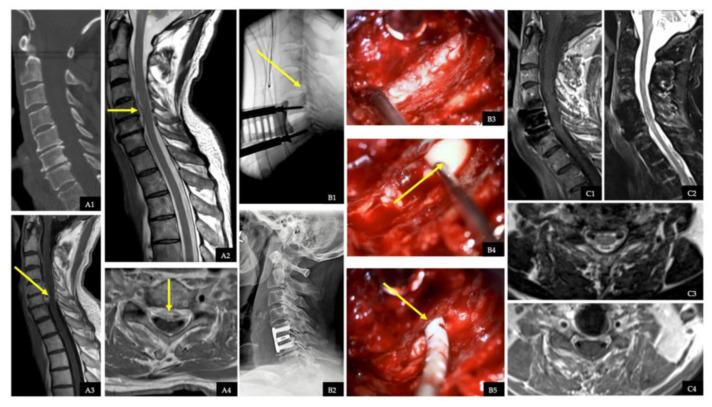

Diagnostics, Management, and Outcomes in Patients with Pyogenic Spinal Intra- or Epidural Abscess.

Owing to the lack of evidence on the diagnostics, clinical course, treatment, and outcomes of patients with extremely rare spinal intradural abscess (SIA) and spinal epidural abscess (SEA), we retrospectively analyzed and compared a cohort of patients to determine the phenotyping of both entities.

Over a period of 20 years, we retrospectively analyzed the electronic medical records of 78 patients with SIA and SEA.

The patients with SIA showed worse motor scores (MS scores) on admission (SIA: 20 ± 26 vs. SEA: 75 ± 34, < 0.001), more often with an ataxic gait (SIA: 100% vs. SEA: 31.8%, < 0.001), and more frequent bladder or bowel dysfunction (SIA: 91.7% vs. SEA: 27.3%, < 0.001) compared to the SEA patients. Intraoperative specimens showed a higher diagnostic sensitivity in the SEA patients than the SIA patients (SIA: 66.7% vs. SEA: 95.2%, = 0.024), but various pathogens such as (SIA 33.3% vs. SEA: 69.4%) and and (SIA 33.3% vs. SEA: 8.1%, = 0.038) were detected in both entities. The patients with SIA developed sepsis more often (SIA: 75.0% vs. SEA: 18.2%, < 0.001), septic embolism (SIA: 33.3% vs. SEA: 8.3%, = 0.043), signs of meningism (SIA: 100% vs. 18.5%, < 0.001), ventriculitis or cerebral abscesses (SIA: 41.7% vs. SEA: 3.0%, < 0.001), and pneumonia (SIA: 58.3% vs. SEA: 13.6%, = 0.002). The mean MS score improved in both patient groups after surgery (SIA: 20 to 35 vs. SEA: 75 to 90); however, the SIA patients showed a poorer MS score at discharge (SIA: 35 ± 44 vs. SEA: 90 ± 20, < 0.001). C-reactive protein (CrP) (SIA: 159 to 49 vs. SEA: 189 to 27) and leukocyte count (SIA: 15 to 9 vs. SEA: 14 to 7) were reduced at discharge. The SIA patients had higher rates of disease-related mortality (SIA: 33.3% vs. SEA: 1.5%, = 0.002), had more pleural empyema (SIA: 58.3% vs. SEA: 13.6%, = 0.002), required more than one surgery (SIA: 33.3% vs. SEA 13.6%, = 0.009), were treated longer with intravenous antibiotics (7 ± 4 w vs. 3 ± 2 w, < 0.001) and antibiotics overall (12 ± 10 w vs. 7 ± 3 w, = 0.022), and spent more time in the hospital (SIA: 58 ± 36 vs. SEA: 26 ± 20, < 0.001) and in the intensive care unit (SIA: 14 ± 18 vs. SEA: 4 ± 8, = 0.002).

Our study highlighted distinct clinical phenotypes and outcomes between both entities, with SIA patients displaying a markedly less favorable disease course in terms of complications and outcomes.